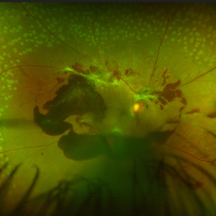

Unstable PDR s/p Laser

Unstable PDR s/p Laser

Aug 4 2025 by Anjana Mirajkar, MS Ophthalmology

Fundus photograph of a 60 year old male with an unstable PDR showing traction at the posterior pole with sub hyaloid hemorrhage. Peripheral PRP marks can be seen.

Photographer: Dr. Anjana Mirajkar- HV Desai eye hospital ,Pune

Imaging device: Optos

Condition/keywords: pan-retinal photocoagulation (PRP), proliferative diabetic retinopathy (PDR), subhyaloid hemorrhage, tractional retinal detachment